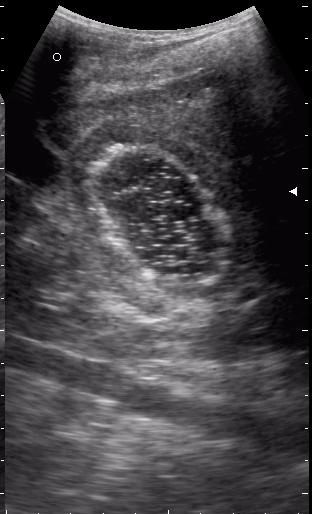

живой эхинококк.